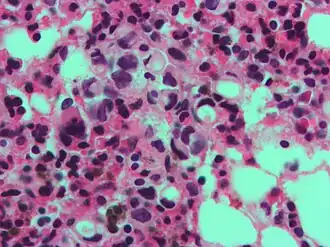

A signet ring-like foamy macrophage, which may mimic a cancer cell, but the texture of the nucleus is similar to that of a normal macrophage. -

High magnification micrograph showing signet ring cells, with clear cytoplasm, in metastatic breast carcinoma. H&E stain. -